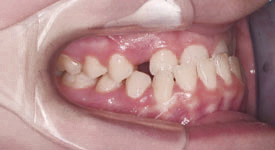

Overbite Side